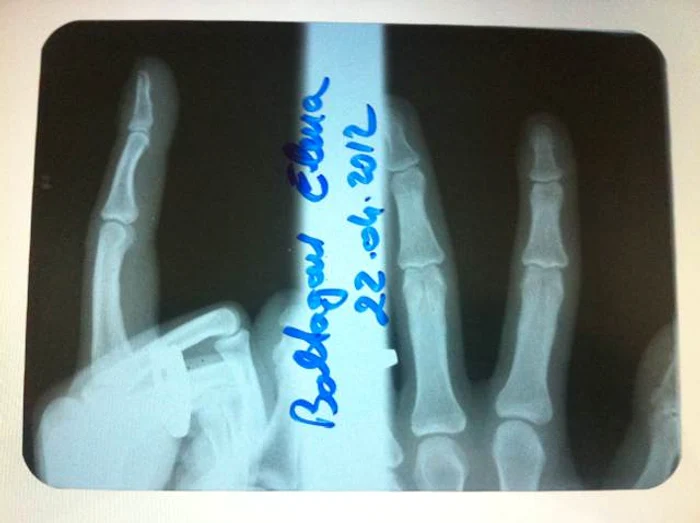

Imediat după spectacol, Ellie s-a retras să semneze autografe, iar la plecare, în învălmășeală, mulțimea a închis ușa la mașină peste mâna cântăreței. Vedeta a fost supusă unor teste si unor radiografii, iar medicii au constatat că aceasta și-a luxat un deget în urma incidentului.

"I-au făcut câteva radiografii și i-au dat un vaccin contra infecției. Din fericire, degetul nu este rupt ci doar luxat. A fost o rană urâtă, iar acum va trebui să stea cu degetul bandajat câteva săptămâni. Din fericire, nu va trebui să anulăm concertele din perioada următoare", declarat Doru Tinca, managerul și iubitul cântăreței pentru agentiadepresamondena.com.